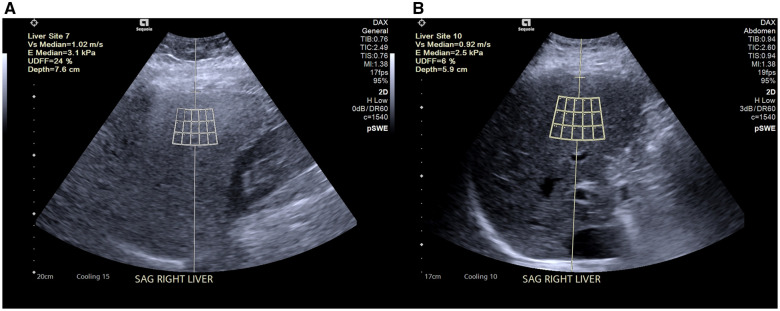

Materials and methods: Participants undergoing bariatric surgery were prospectively enrolled at a single center and evaluated at 3 time points: pre-surgery (before a 2-week pre-operative liquid diet), day of surgery (immediately following the liquid diet), and 6 months post-surgery. Measurements included UDFF (Siemens Healthineers ACUSON SEQUOIA), skin-to-liver capsule thickness, serum metabolic tests, liver function tests, and anthropometric data. Changes in these variables were analyzed using 2-sided paired t-tests. Pearson correlation analysis was used to evaluate associations between changes in UDFF and changes in skin-to-capsule thickness, waist circumference, and BMI.

Results: Seventeen participants (mean age 47.41 ± 11.11 years, 15 women) completed the study. UDFF (mean ± SD) decreased significantly from 20.4 ± 8.41% pre-surgery to 11.08 ± 6.33% at 6 months post-surgery (P < .001). Skin-to-liver capsule thickness decreased from 4.06 ± 0.66 cm to 2.88 ± 0.55 cm (P < .001). BMI decreased from 46.27 ± 6.65 kg/m2 to 35.5 ± 6.64 kg/m2 (P < .001), and waist circumference decreased from 130.29 ± 13.49 cm to 111.98 ± 16.03 cm (P < .001). No significant changes were observed in UDFF, skin-to-liver capsule thickness, or waist circumference after the liquid diet phase. Strong positive correlation between UDFF and BMI reduction was observed (r = 0.75, P < .001).

Conclusions: Bariatric surgery results in significant reductions in hepatic steatosis, as measured by UDFF, and reductions in skin-to-liver capsule thickness, BMI, and waist circumference at 6 months post-surgery. These findings suggest that UDFF could meet the clinical need for noninvasive monitoring of hepatic steatosis following bariatric surgery.